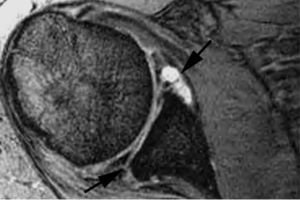

Lesión de Perthes

La lesión de Perthes es similar a la de Bankart, con la excepción de que no existe rotura capsuloperióstica, aunque el periostio puede estar separado del borde anterior del margen glenoideo (fig. 10). Esta lesión puede ser difícil de visualizar, incluso con artrorresonancia, a menos que se obtengan imágenes con la posición de abducción y rotación externa (ABER). En un estudio de 10 casos, verificados quirúrgicamente, Wisher et al17 comprobaron que el 50% de las lesiones de Perthes sólo podían visualizarse en la posición de ABER.

Fig. 10.--Lesión de Perthes. Artrorresonancia T1 con saturación grasa en posición ABER (abducción y rotación externa), donde se observa un arrancamiento parcial del labio glenoideo (flecha) con conservación de la unión capsuloperióstica.